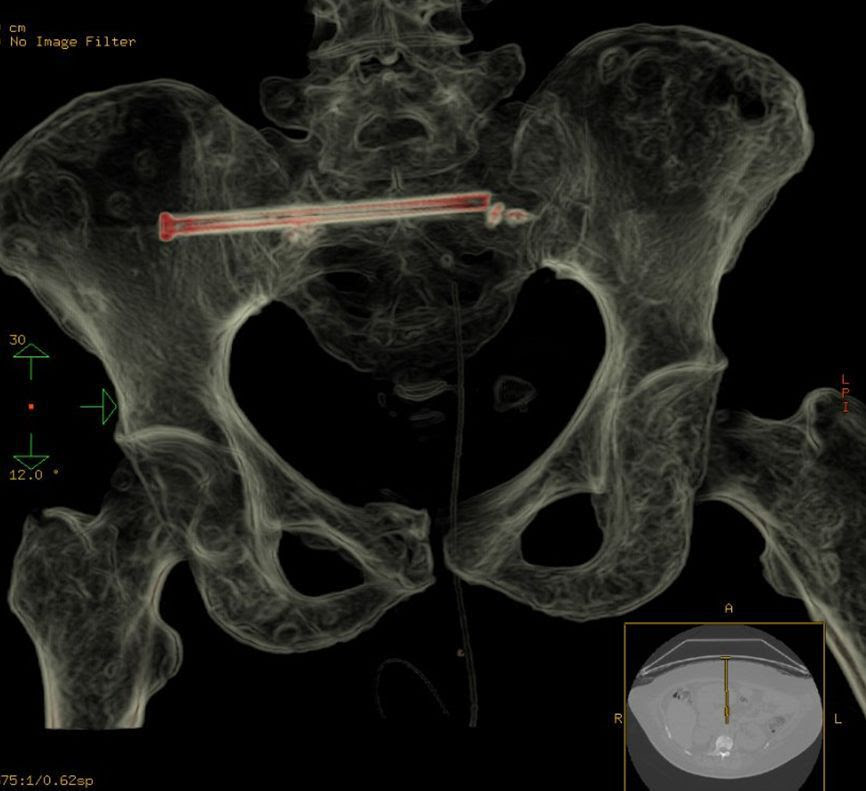

A specialized medical team at King Fahd Medical City in the capital Riyad succeeded Wednesday 12th October in repairing a fracture of the sacral bone in the pelvic area of a cancer patient by a metal screw using interventional radiology without surgery.

A spokesperson for the 2nd Riyadh Health Cluster stated that the female patient diagnosed with stage 4 breast cancer suffered from pain in her lower back and had difficulties standing and sitting. After several x-rays and examinations, it was found that she suffered from fractures in more than one area, including the pelvic region.

The team who includes bone-muscle radiology and interventional nonvascular radiology consultants found that the best way to treat the case was to stabilize the fracture to relieve pain and facilitate rehabilitation exercises.

The technique used began years ago and proved its success for patients who could not undergo surgery due to their critical conditions such as osteoporosis. The procedure is done through an incision in the skin of 2 to 3 mm under local or general anesthesia, and it takes about two hours to fully conclude each session.